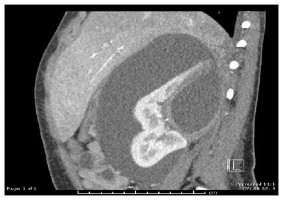

Hématome au rein (coupe sagittale).